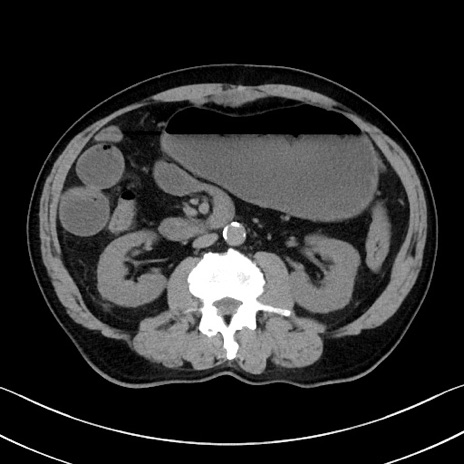

症例35(横断像)

【症例】70歳代 男性

【主訴】腹部膨満、嘔吐

【現病歴】昨日より腹部膨満感出現。本日増悪し、仙痛出現。嘔吐あり、受診。

【既往歴】糖尿病、胆摘後

【身体所見】BP 149/80mmHg、HR 74/min、BT 35.9℃、腹部:膨満、軟、圧痛なし。腸雑音減弱あり。上腹部正中切開瘢痕あり。

【データ】WBC 13500、CRP 1.72